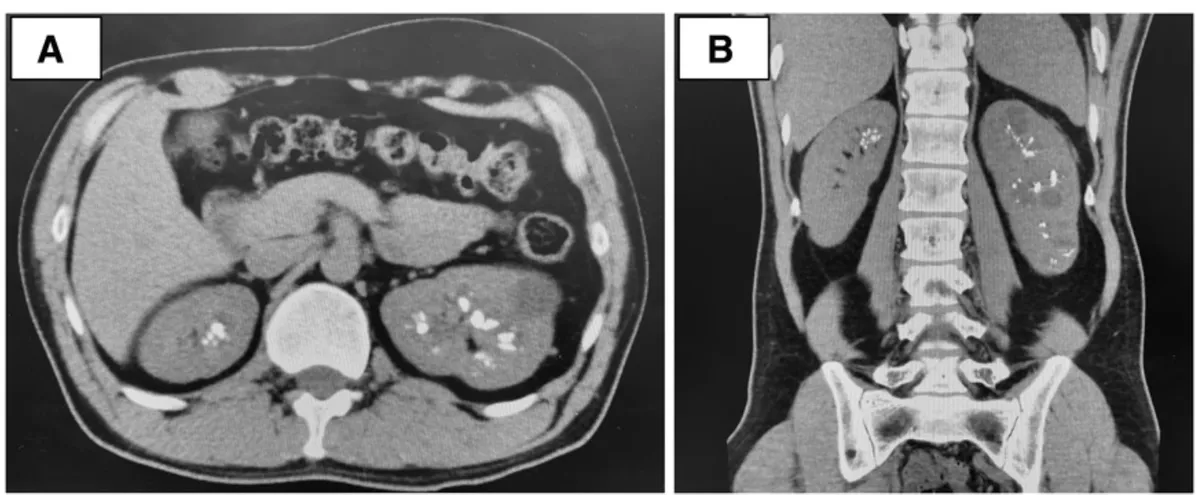

Os achados da TC sem contraste revelaram rins aumentados de tamanho, múltiplos cistos renais e nefrocalcinose (Figura 1).

Os achados tomográficos com contraste mostraram um aspecto de "buquê de flores" na fase excretora (Figura 2).

A síndrome de Beckwith-Wiedemann é uma das causas do rim espongiomedular, que se apresenta comachados específicos na tomografia computadorizada, incluindo nefrocalcinose medular, dilatação cística e um padrão de estrias semelhantes a buquês de flores nas papilas renais.